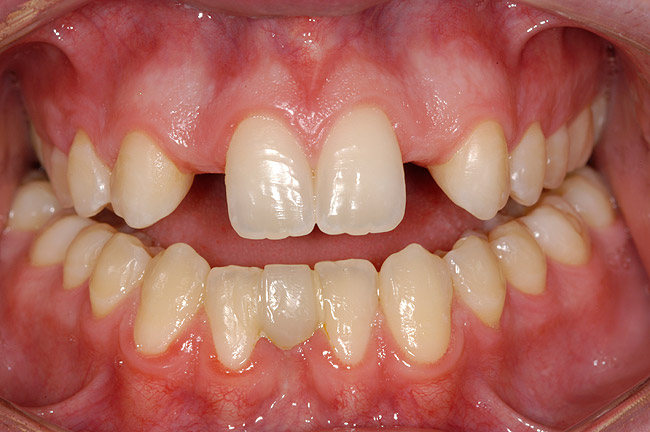

Figure 1 A patient presents after completion of orthodontic treatment for restorative enhancement of microdontic maxillary lateral incisors.

Figure 1